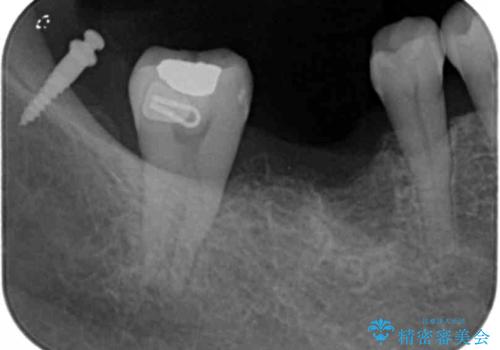

薄い歯質の歯牙に過大な負荷がかかり亀裂を生じ大臼歯分岐部に大きな骨吸収を認め、抜歯を余儀なくされる状態です。

抜歯を行ったのち前後の歯に軽度の動揺があるため、インプラントではなくブリッジによる補綴処置を行い機能回復を行いますが、近心傾斜した第2大臼歯をマイクロインプラントを用いた小矯正を行うことで歯軸方向を改善し、神経を温存した状態でブリッジ製作できるよう前処置を行います。